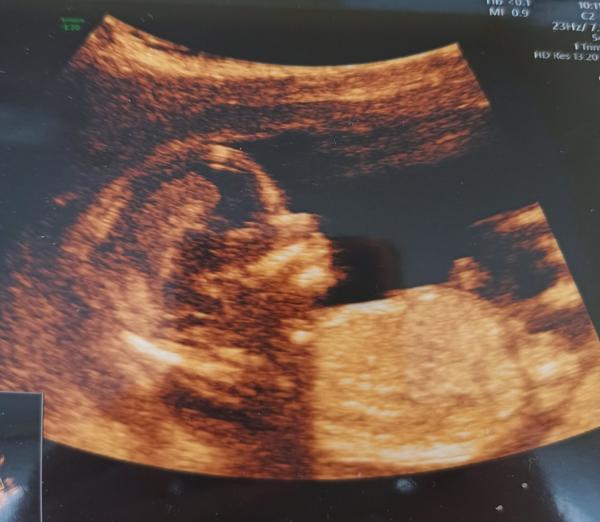

Foto 17tt ze screengu, ještě 20tt na screeningu mi řekl že kluk. Jenomže v pátek jdu opět je svému doktorovi 27tt a on že holka a trvá na tom od začátku. Hledal, udělal mi 4 fotky a pinďa prostě nikde!!! Je možné, že to pinďa nebyl??? Děkuji za názor